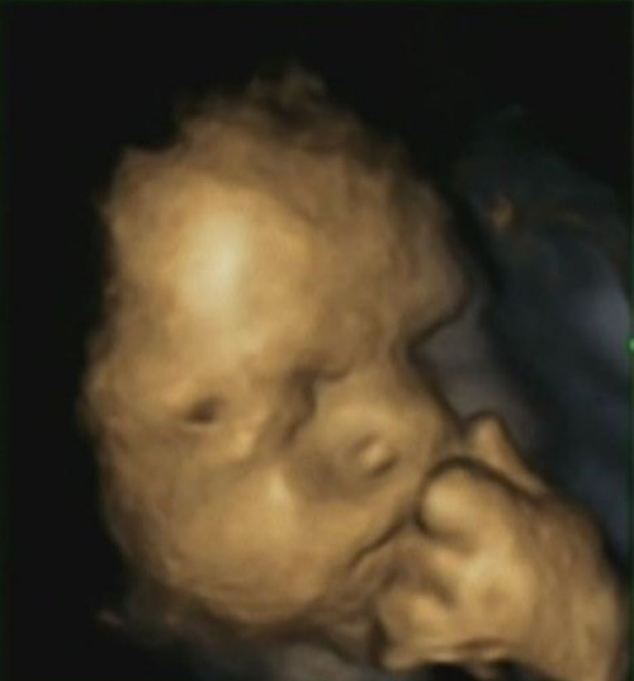

Hình ảnh siêu âm 3D cho các mẹ bầu có thể ngắm nhìn đứa con yêu của mình từ trong bụng mẹ. Tuy nhiên, hình ảnh bàn tay thai nhi chống cằm lại cho thấy, bé đang chịu ảnh hưởng từ sự căng thẳng của người mẹ.

| Hình ảnh bàn tay thai nhi chống cằm cho thấy, bé đang chịu ảnh hưởng từ sự căng thẳng của người mẹ. Ảnh: Dailymail. |

Kết quả cho thấy, 8 bé gái và 7 bé trai đưa tay lên mặt tổng cộng 342 lần. Các bà mẹ càng lo lắng, số lần thai nhi đưa tay lên trán càng tăng, theo báo cáo của tiến sĩ Reissland trên tạp chí Laterality: Asymmetries of Body, Brain and Cognition. Tiến sĩ Reissland tin rằng, các bé đưa tay lên trán khi lượng hormone cortisol trong cơ thể các bà mẹ tăng lên.